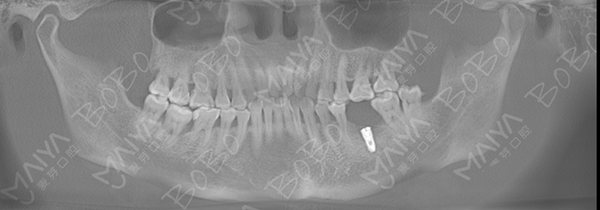

赵阿姨拍摄口腔全景ct

口腔ct全景片

术后口腔全景ct